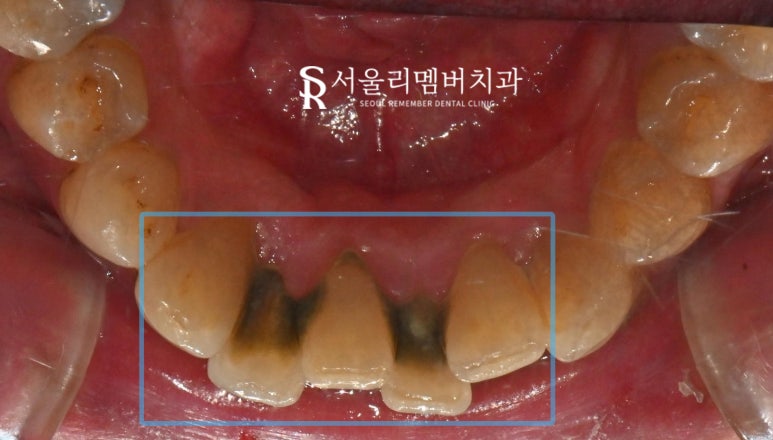

Before / After

서울대입구역 치과

이가 뻐근하고 색이 변했다며 내원하셨던 분인데요.

육안으로 관찰을 해볼까요?

우선 정면 사진을 보면 자연치 표면 곳곳에

점과 같은 이물질이 붙어 있습니다.

바로 치석이였죠..

여기저기 이 사이에 누렇게 껴있는 것들을 비롯해

좀 더 자세히 살펴보기 위해 설면(반대쪽)을 관찰했더니..

검게 변한 다량의 치석이 쌓여 있었습니다.

이렇게 심하게 쌓여 있는 것들은

치주 질환을 비롯한 구강 염증이나

갑자기 생긴 입 냄새의 원인이 될 수 있습니다.

서울대입구역 치과 에서

곧바로 스케일링을 통해 과도하게 쌓인 이물질들을

깨끗하게 청소해 줘야 되겠군요!

약 30분 정도가 지난 뒤,

모든 과정이 마무리되었습니다.

전과 비교했을 때 확연히 깨끗해진 것이 관찰되네요.